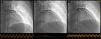

Figure 2.

Acute thrombosis of the right coronary artery, TIMI flow 0 (a); status following stent implantation, TIMI flow 3 (b).

Figure 3.

Acute thrombosis of the left anterior descending artery, TIMI flow 0 (a); spontaneous reperfusion revealing a massive thrombus in segment 7 (b); status following stent implantation, TIMI flow 3 (c).

The coronary angiogram showed simultaneous acute thrombosis of the right coronary artery (RCA) (Figure 2a) and of the left anterior descending (LAD) artery (Figure 3a). Initially, to visualize suspected plaque rupture and to aid the decision whether to implant stents, multiple aspiration thrombectomies were performed, resulting in removal of substantial amounts of thrombotic material (Figure 4). After intravenous and intracoronary administration of abciximab, an everolimus-eluting stent was implanted into the RCA, restoring good epicardial coronary flow (Figure 2b). In the LAD spontaneous reperfusion occurred, revealing a massive thrombus (Figure 3b). After aspiration thrombectomy, a stent was implanted (Figure 3c). Echocardiographic examination revealed inferior wall and basal septal akinesis with ejection fraction of 35%. Right ventricular enlargement (5.4 cm in apical 4-chamber view) and hypokinesis (tricuspid annular plane systolic excursion [TAPSE] 14 mm) were present. Right ventricular function was improved on control echocardiography (TAPSE 27 mm).